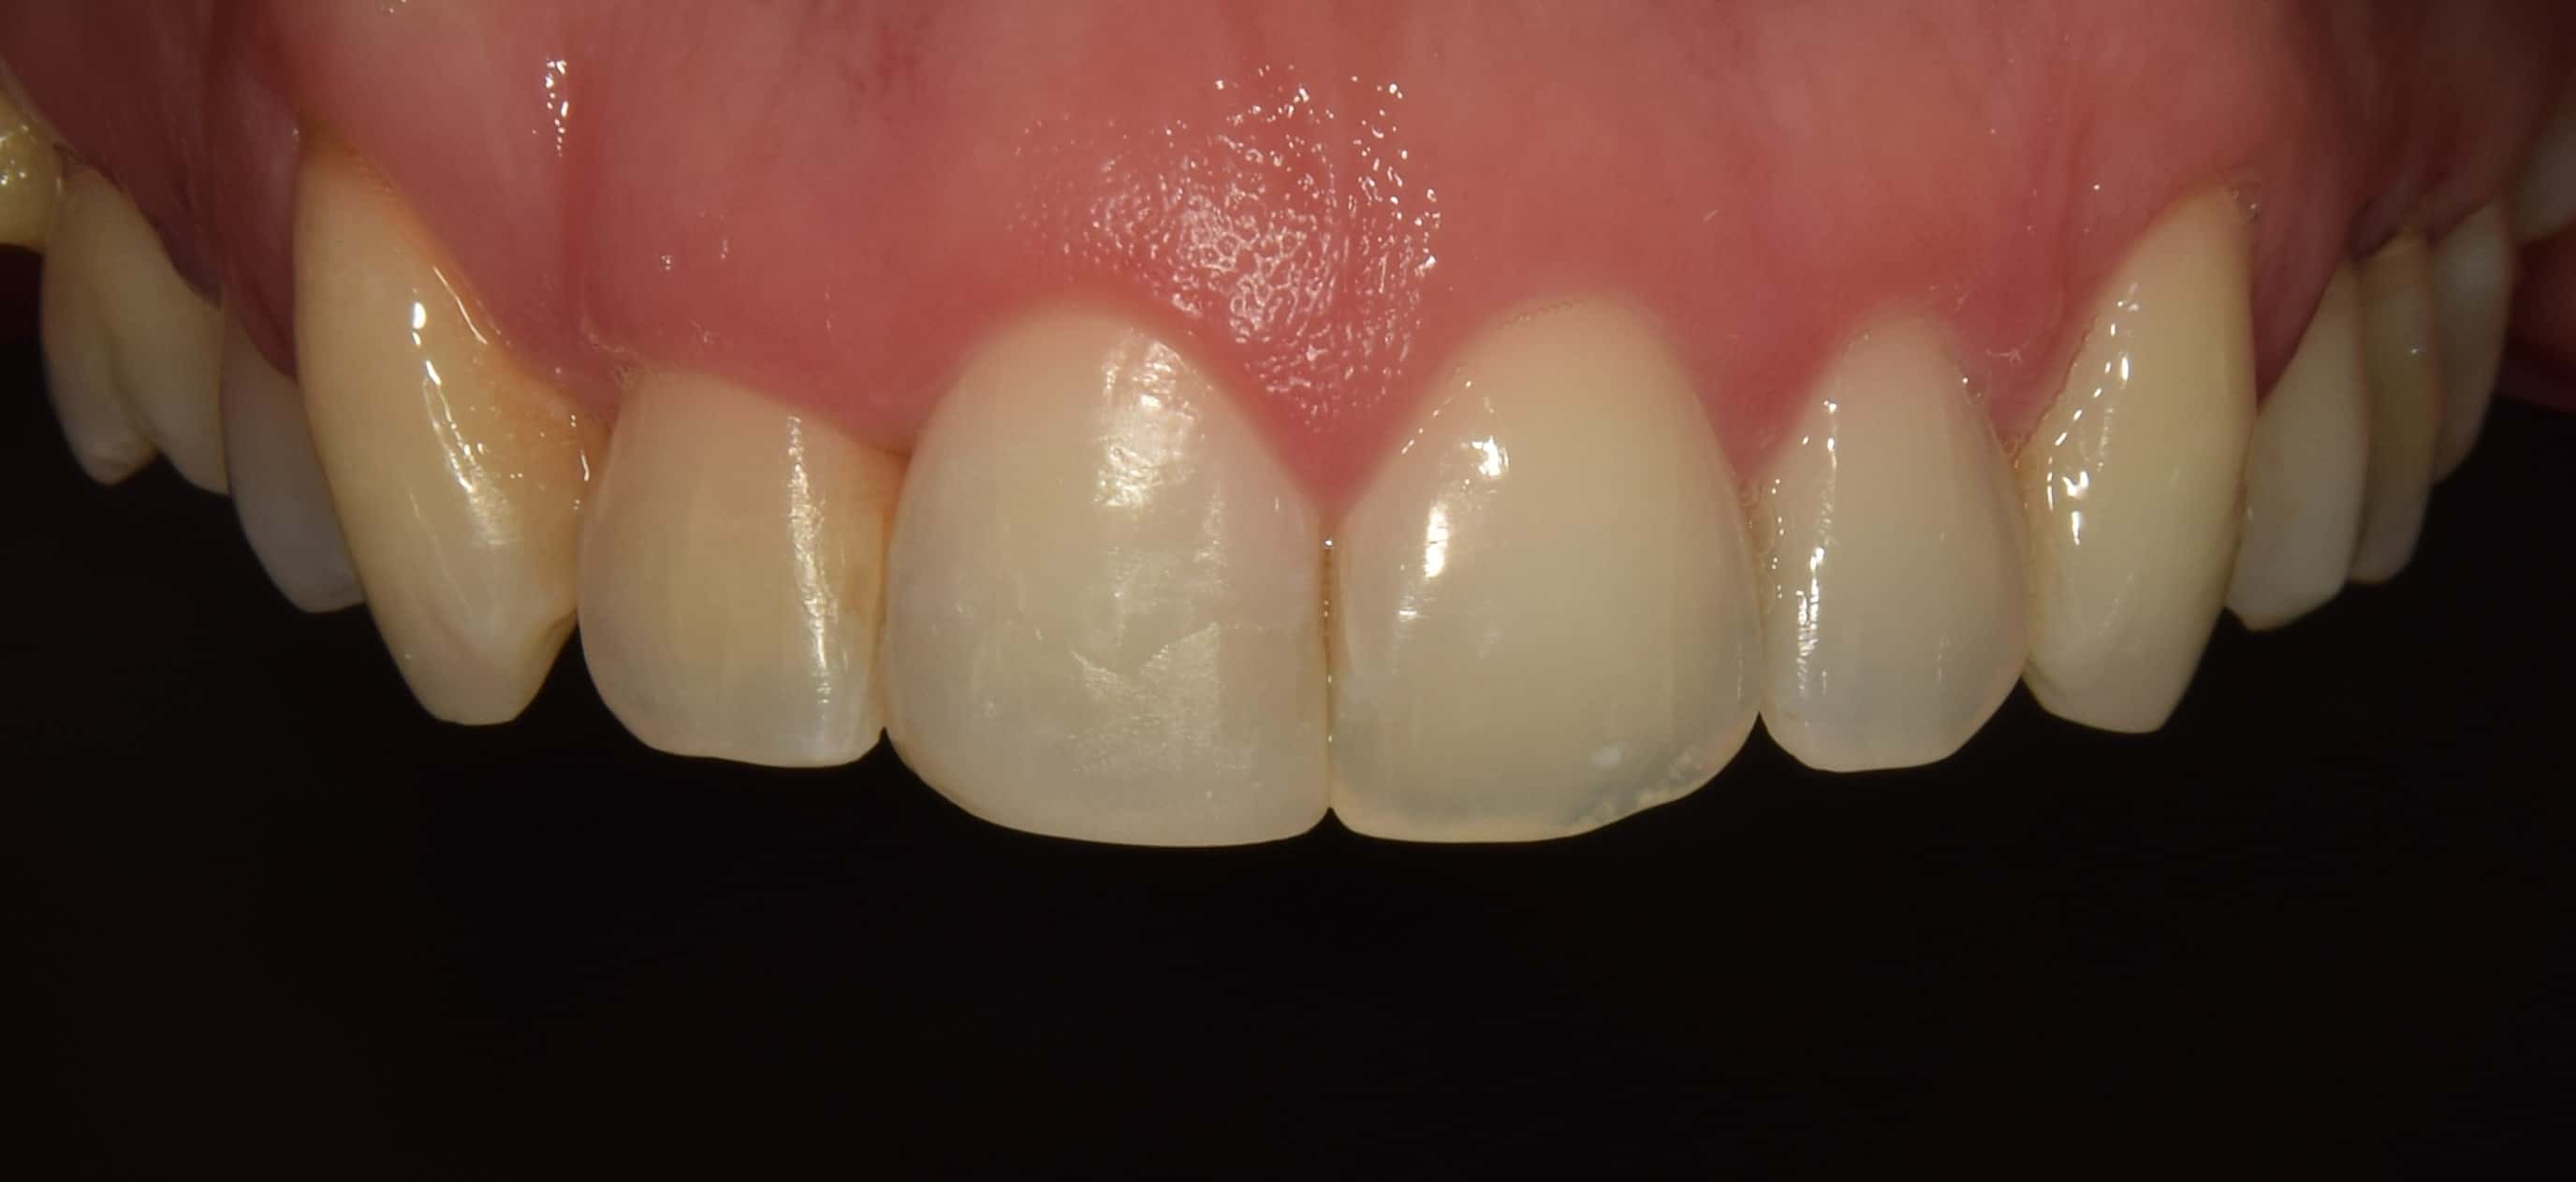

Bálint a 90 fokban elfordult jobb felső kismetszője miatt keresett meg engem. A vizsgálatokat követően kiderült, hogy a probléma ennél jóval komplexebb: súlyos keresztharapást, súlyos mélyharapást és felső rágósík billenést diagnosztizáltam nála. Alsó-felső H4 önligírozó fogszabályozó készülék, intermaxilláris gumihúzás és elülső harapásemelők segítségével korrigáltuk az eltéréseket. A bal oldali rágósík billenést fogszabályzási miniimplantátum alkalmazásával oldottuk meg. A bal felső-elülső fogakat felfelé mozgattuk, a miniimplantátumhoz húzva. Bálint esete igen komplex volt, ám kiváló együttműködésének köszönhetően 26 hónap alatt végeztünk a kezelésével (beleértve a 2-3 hónapos COVID-19 miatti leállást is). Az eredmény úgy gondolom magáért beszél!